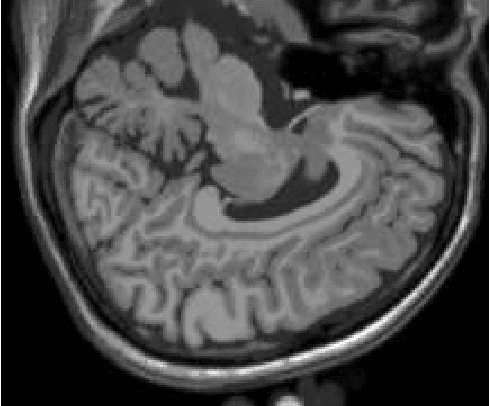

Abstract:Alzheimer's disease is the most common cause of dementia, yet difficult to accurately diagnose without the use of invasive techniques, particularly at the beginning of the disease. This work addresses the classification and analysis of multispectral synthetic images composed by diffusion-weighted magnetic resonance brain volumes for evaluation of the area of cerebrospinal fluid and its correlation with the progression of Alzheimer's disease. A 1.5 T MR imaging system was used to acquire all the images presented. The classification methods are based on multilayer perceptrons and classifiers of radial basis function networks. It is assumed that the classes of interest can be separated by hyperquadrics. A polynomial network of degree 2 is used to classify the original volumes, generating a ground-truth volume. The classification results are used to improve the usual analysis by the map of apparent diffusion coefficients.

Abstract:Multispectral image analysis is a relatively promising field of research with applications in several areas, such as medical imaging and satellite monitoring. A considerable number of current methods of analysis are based on parametric statistics. Alternatively, some methods in Computational Intelligence are inspired by biology and other sciences. Here we claim that Philosophy can be also considered as a source of inspiration. This work proposes the Objective Dialectical Method (ODM): a method for classification based on the Philosophy of Praxis. ODM is instrumental in assembling evolvable mathematical tools to analyze multispectral images. In the case study described in this paper, multispectral images are composed of diffusion-weighted (DW) magnetic resonance (MR) images. The results are compared to ground-truth images produced by polynomial networks using a morphological similarity index. The classification results are used to improve the usual analysis of the apparent diffusion coefficient map. Such results proved that gray and white matter can be distinguished in DW-MR multispectral analysis and, consequently, DW-MR images can also be used to furnish anatomical information.

Abstract:The unsupervised classification has a very important role in the analysis of multispectral images, given its ability to assist the extraction of a priori knowledge of images. Algorithms like k-means and fuzzy c-means has long been used in this task. Computational Intelligence has proven to be an important field to assist in building classifiers optimized according to the quality of the grouping of classes and the evaluation of the quality of vector quantization. Several studies have shown that Philosophy, especially the Dialectical Method, has served as an important inspiration for the construction of new computational methods. This paper presents an evaluation of four methods based on the Dialectics: the Objective Dialectical Classifier and the Dialectical Optimization Method adapted to build a version of k-means with optimal quality indices; each of them is presented in two versions: a canonical version and another version obtained by applying the Principle of Maximum Entropy. These methods were compared to k-means, fuzzy c-means and Kohonen's self-organizing maps. The results showed that the methods based on Dialectics are robust to noise, and quantization can achieve results as good as those obtained with the Kohonen map, considered an optimal quantizer.

Abstract:The materialist dialectical method is a philosophical investigative method to analyze aspects of reality. These aspects are viewed as complex processes composed by basic units named poles, which interact with each other. Dialectics has experienced considerable progress in the 19th century, with Hegel's dialectics and, in the 20th century, with the works of Marx, Engels, and Gramsci, in Philosophy and Economics. The movement of poles through their contradictions is viewed as a dynamic process with intertwined phases of evolution and revolutionary crisis. In order to build a computational process based on dialectics, the interaction between poles can be modeled using fuzzy membership functions. Based on this assumption, we introduce the Objective Dialectical Classifier (ODC), a non-supervised map for classification based on materialist dialectics and designed as an extension of fuzzy c-means classifier. As a case study, we used ODC to classify 181 magnetic resonance synthetic multispectral images composed by proton density, $T_1$- and $T_2$-weighted synthetic brain images. Comparing ODC to k-means, fuzzy c-means, and Kohonen's self-organized maps, concerning with image fidelity indexes as estimatives of quantization distortion, we proved that ODC can reach almost the same quantization performance as optimal non-supervised classifiers like Kohonen's self-organized maps.

Abstract:Alzheimer's disease is the most common cause of dementia, yet hard to diagnose precisely without invasive techniques, particularly at the onset of the disease. This work approaches image analysis and classification of synthetic multispectral images composed by diffusion-weighted magnetic resonance (MR) cerebral images for the evaluation of cerebrospinal fluid area and measuring the advance of Alzheimer's disease. A clinical 1.5 T MR imaging system was used to acquire all images presented. The classification methods are based on multilayer perceptrons and Kohonen Self-Organized Map classifiers. We assume the classes of interest can be separated by hyperquadrics. Therefore, a 2-degree polynomial network is used to classify the original image, generating the ground truth image. The classification results are used to improve the usual analysis of the apparent diffusion coefficient map.